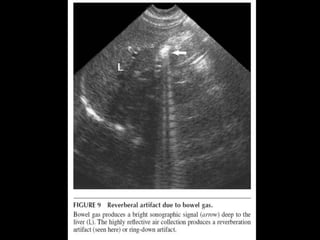

BEST INITIAL TEST?

• ULTRASONOGRAPHY : bright echogenic

crescent in the gallbladder fossa with dirty

shadowing and ring down artifacts.

– Similar:

• Contracted stone-filled gallbladder (WES)

• Porcelain gallbladder w/ calcified wall due to chronic

cholecystitis

• CONFIRMATION:

– Abdominal rx or CT

BEST INITIAL TEST? •ULTRASONOGRAPHY : bright echogenic crescent in the gallbladder fossa with dirty shadowing and ring down artifacts. – Similar: • Contracted stone-filled gallbladder (WES) • Porcelain gallbladder w/ calcified wall due to chronic cholecystitis • CONFIRMATION: – Abdominal rx or CT